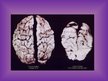

Smadzeņu izskats